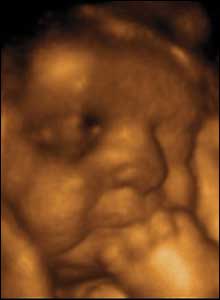

22 týdnů, 21 cm

Ve 22 týdnech jsou děti schopny jemných pohybů rukou a prsty. Na krátkou chvíli se pozorované dítě škrámalo, mnulo a dotýkalo brady a nosu.